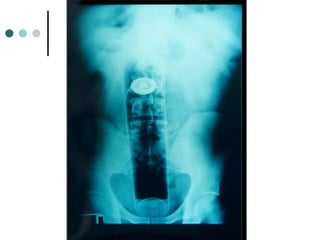

RADIOGRAFÍA SIMPLE

La radiografía de abdomen

simple de pie muestra

niveles hidroaéreos.

RAYOS ABD SIMPLE : OBSTRUCION ALTA

OBSTRUCCION INTESTINAL ALTA POR...